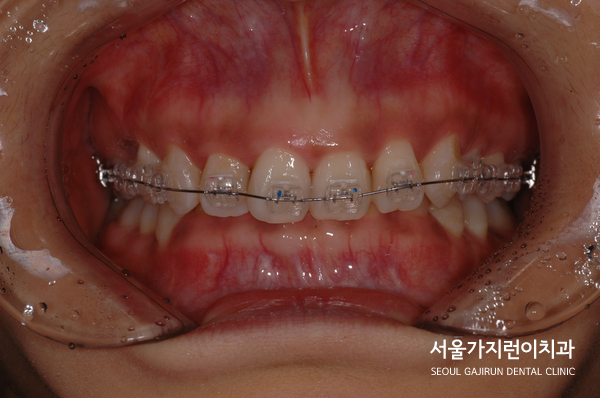

그래서 상기 환자의 경우 상악 전치의 전돌을 해소하기 위해

미니스크류를 사용한 치아교정이 이루어졌는데요.

설측탄댐방식을 이용해 치아이동에 필요한 힘을 충분히 줄 수 있었습니다.